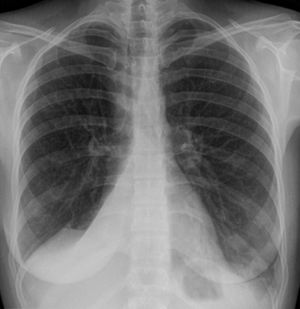

| همود في الرئة اليمنى لمريض. | |

همود الرئة أو انخماص الرئة Atelectasis، هو انهيار أو فشل في الرئة ناتج عن انخفاض أو غياب تبادل الغازات. قد يؤثر همود الرئة على الرئة بالكامل أو جزء منها.[2] عادة ما يحدث في إحدى الرئتين. حيث تكون فيه الحويصلات الهوائية فارغه من الهواء. و ما يميزه عن التصلب الرئوي هو أن انخماص الرئة تكون فيه الحويصلات الهوائية منكمشة.